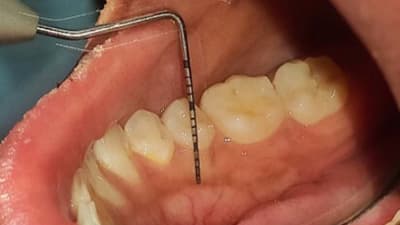

Often times patients present with an immediate concern, however other underlying problems may exist that might also need to be addressed in order to fully resolve the issue.

This article presents a clinical case of a comprehensive full-mouth rehabilitation in a 26-yearold female patient with an anterior open bite and accompanying mild chronic generalized periodontitis.